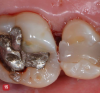

Fig 12. Microislands of calculus are shown on the root surface (arrows on some of the microislands) after scaling with an ultrasonic scaler and sharp hand curettes. This root surface had been judged “clean” when observed with 3.5x loupes. When viewed with the high magnification of the videoscope, the remaining calculus became obvious. Burnishing with EDTA will remove these microislands of calculus.

Figure 12